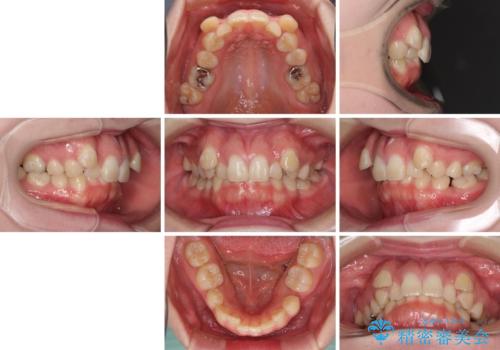

著しい八重歯を短期間で改善 ワイヤー装置による抜歯矯正

- 八重歯と下顎小臼歯の欠損を気にして来院された患者様です。

下顎小臼歯の欠損により過蓋咬合となっていたため、下顎は臼歯を起こすことで咬み合わせを改善し、八重歯は第一小臼歯2本を抜歯し、補助装置を使用して速やかに改善することとしました。

著しい過蓋咬合の改善が必要であった割には、治療期間は2年強と標準的でした。

八重歯は3,4か月で速やかに改善されました。